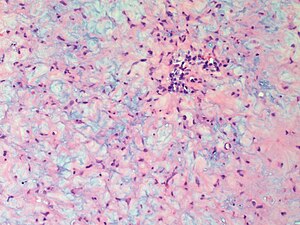

Chondromyxoid fibroma. H&E stain. | |

| LM | spindle cells or stellate cells in a myxoid or chondroid stroma, lobules with hypocellular centers and hypercellular peripheries, +/-giant cells in the hypercellular periphery, scattered calcifications, no true hyaline cartilage formation, no mitotic activity |

Features:[3]

- Spindle cells or stellate cells in a myxoid or chondroid stroma.

- Lobules with hypocellular centers and hypercellular peripheries.

- Giant cells in the hypercellular periphery.

- Scattered calcifications.

- No true hyaline cartilage formation.

- No mitotic activity.